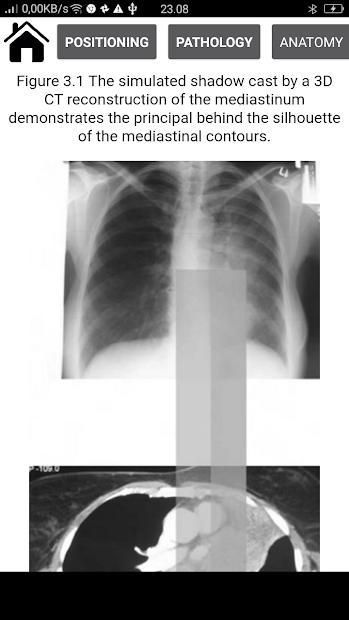

> The silhouette sign

> Suggested scheme for reading a frontal CXR